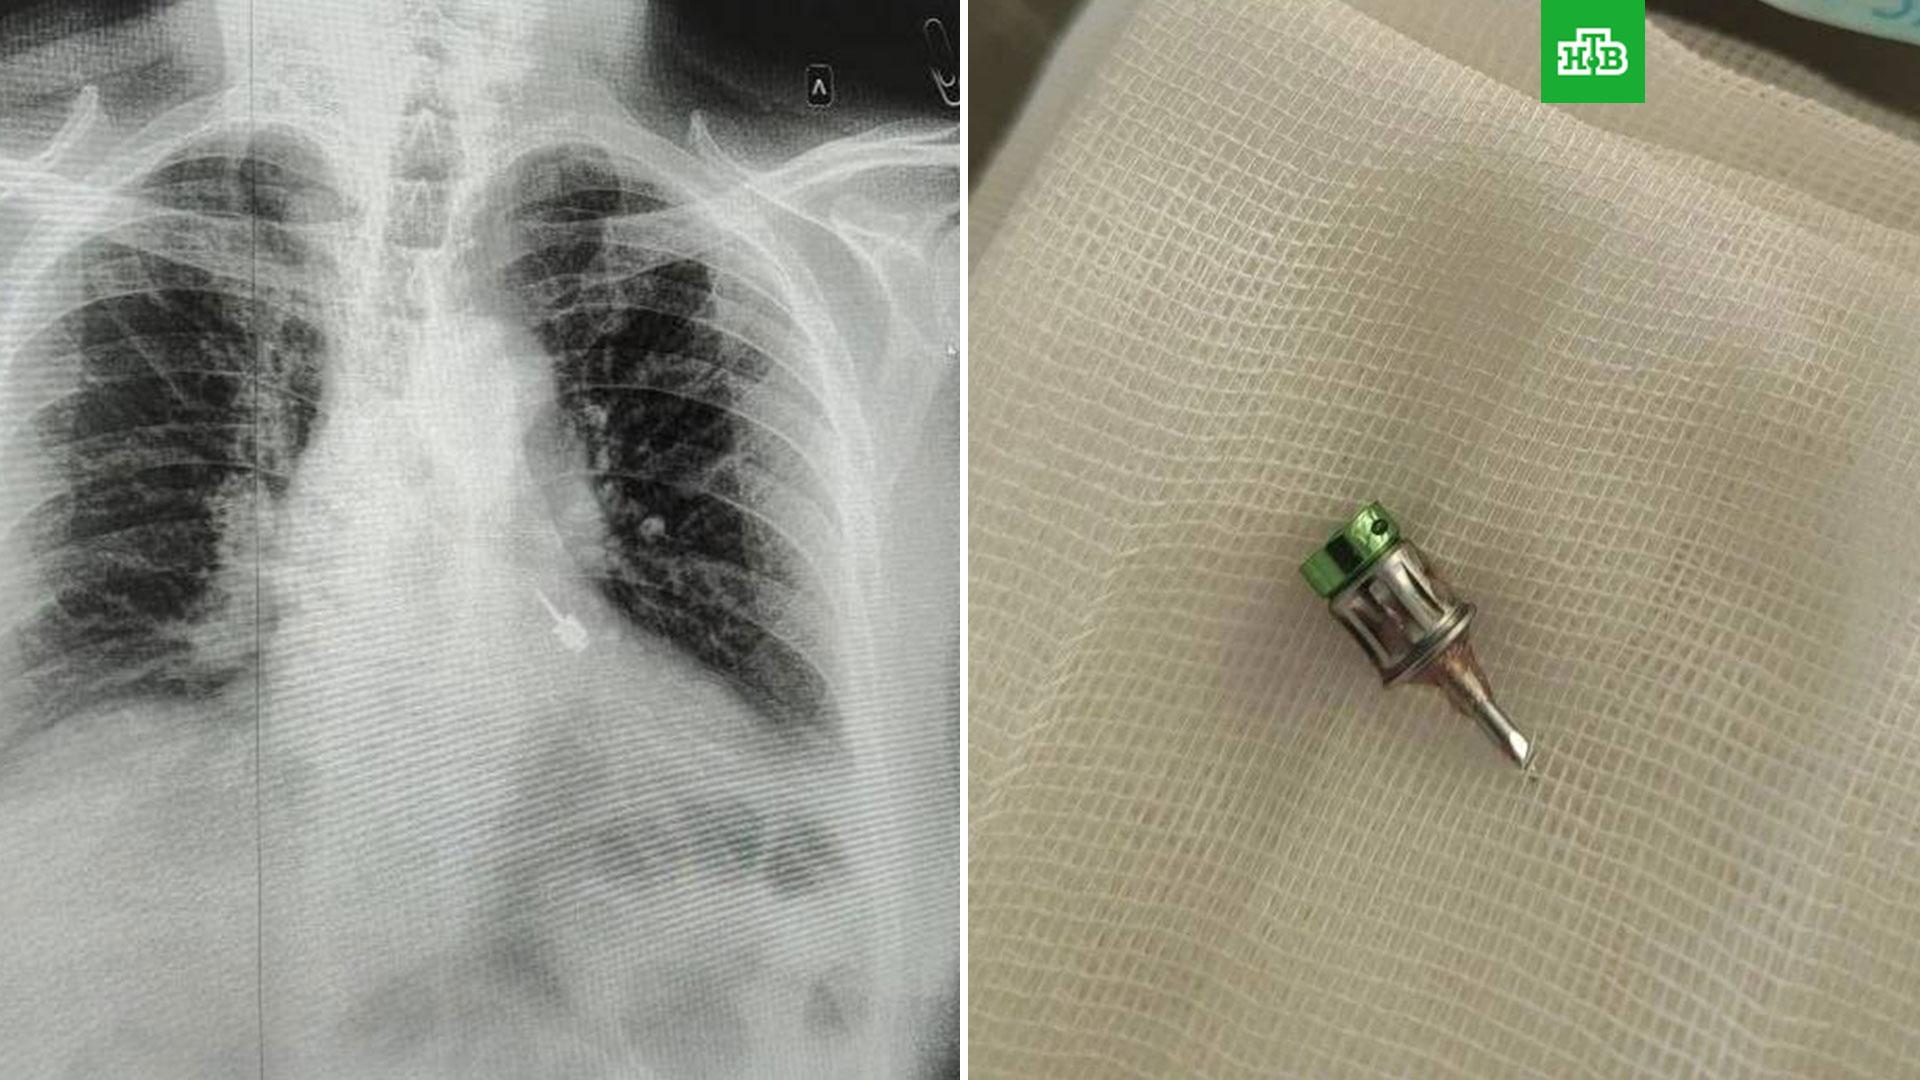

Врачи выяснили, что бор находится в левом бронхе, и экстренно провели бронхоскопию. Медики аккуратно извлекли стоматологический инструмент, не повредив ткани дыхательных путей.